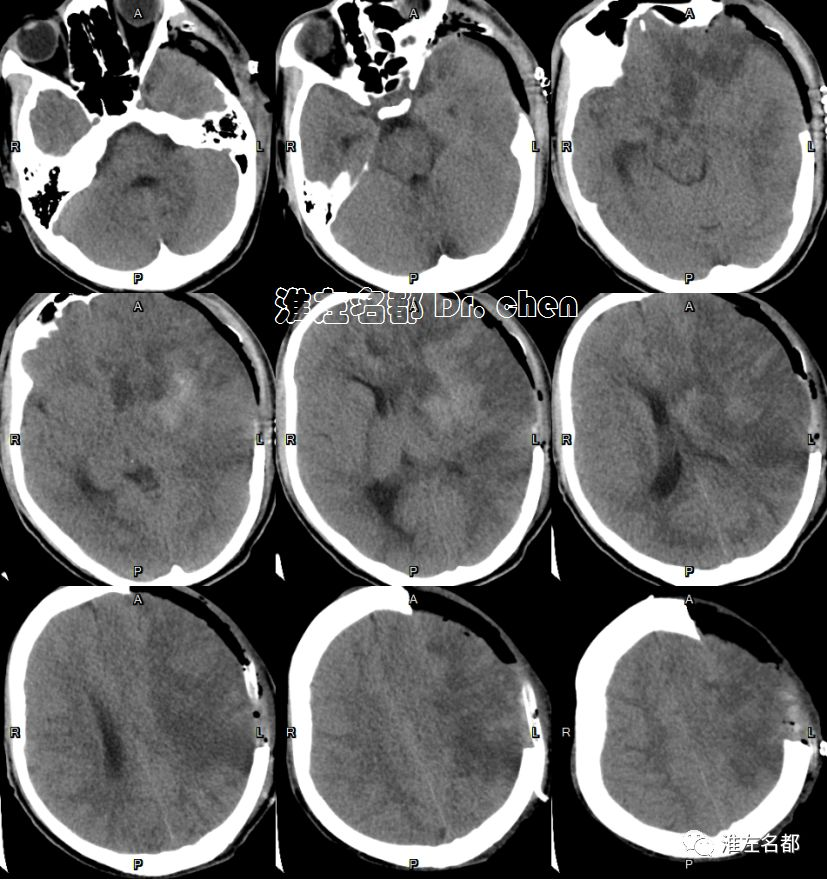

复查CT

2019-9-1 11:34

△颅脑CT平扫+增强:左侧基底节区和部分额叶呈稍高密度,左侧前循环血流通畅;左侧半球肿胀明显,脑室、脑沟和脑池受压,中线结构向右侧显著移位。

复查多模式CT

2019-9-2 11:47

△头颅CT平扫:左侧去骨瓣减压术后,左侧半球仍有肿胀,中线结构移位较前稍改善。

△头颅CTA:左侧前循环管腔通畅,未见明显狭窄。

△脑CTP:左侧额叶CBV和CBF仍然较对侧显著降低(无复流)